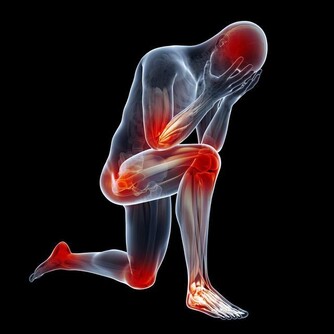

1、適量運動,健康減肥:每週運動3-5天,每次超過30分鐘,以有氧運動為主,通過身體出汗而達到消耗脂肪的目的,具體的項目還要因人而異。但是要提醒一點,如果肝臟脂肪堆積較多時,減肥速度不宜過快。